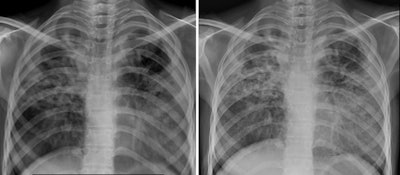

To that end, the group tested image quality as evaluated by two radiologists between a model called Mine 2 (LabIndia Healthcare), a portable handheld x-ray system weighing 1.8 kg, and digital x-ray units routinely used in their health facilities.

The researchers recruited 100 participants with suspected pulmonary TB from outpatient clinics and a community health center in Agra. Each participant underwent two chest x-rays, once with each type of system. Both sets of deidentified images were then independently read by two radiologists blinded to the type of machine used. The primary outcome was agreement between the quality of images produced by the two systems.

According to the findings, the intraobserver (radiologist) agreements regarding the status of 15 chest x-ray parameters between the images ranged between 74% and 100%, with an unweighted mean of 87.2%, the group reported. In addition, in an overall comparison of image quality (on a scale of one to 10, with 10 denoting highest quality), the handheld x-ray images had a score of 9 and the digital chest x-ray images had a score of 8, the researchers stated.

"The current study shows that a handheld x-ray machine, which is easy to use and can potentially be carried to any area, produces x-ray images with quality that is comparable to digital x-ray machines routinely used," the group wrote.